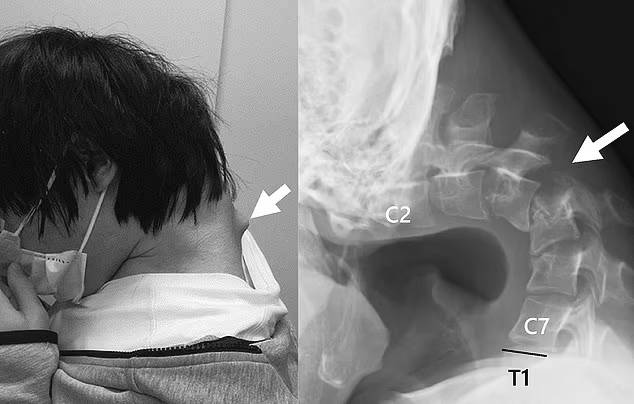

장시간 스마트폰 사용으로 인해 목뼈가 굳은 청년 [사진 출처 = 데일리메일]

일본의 한 20대 청년이 장시간 스마트폰 게임에 몰두하다가 목뼈가 약 90도 꺾이는 희귀 증상인 ‘머리떨굼 증후군’에 걸린 사례가 전해졌습니다.

진단 결과 그의 경추는 탈구된 상태였으며, 시간이 지나면서 척추 주위에 흉터처럼 굳은 조직까지 형성된 것으로 확인됐습니다.

[사진 출처 = 데일리메일]